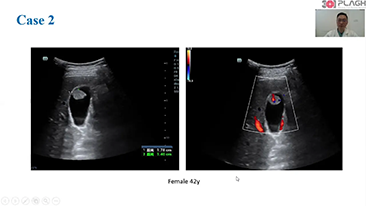

Solusi Pencitraan Umum Resona dari Mindray membantu para dokter mewujudkan diagnosis dan hasil pengobatan yang lebih akurat dan efisien melalui pemerik aplikasi subdivisi yang komprehensif dan alat bantu aplikasi klinis yang efisien.